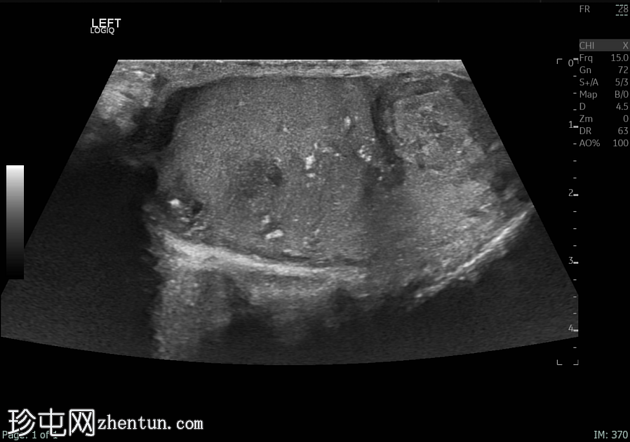

超声检查

纵切面

左侧睾丸肿大,体积约56 mL,可见弥漫性微结石,以及三个内部等回声病灶,伴囊性变、微钙化和明显血流信号,最大病灶大小约4.8 x 3.2 cm。

未见腹主动脉旁或髂淋巴结肿大。